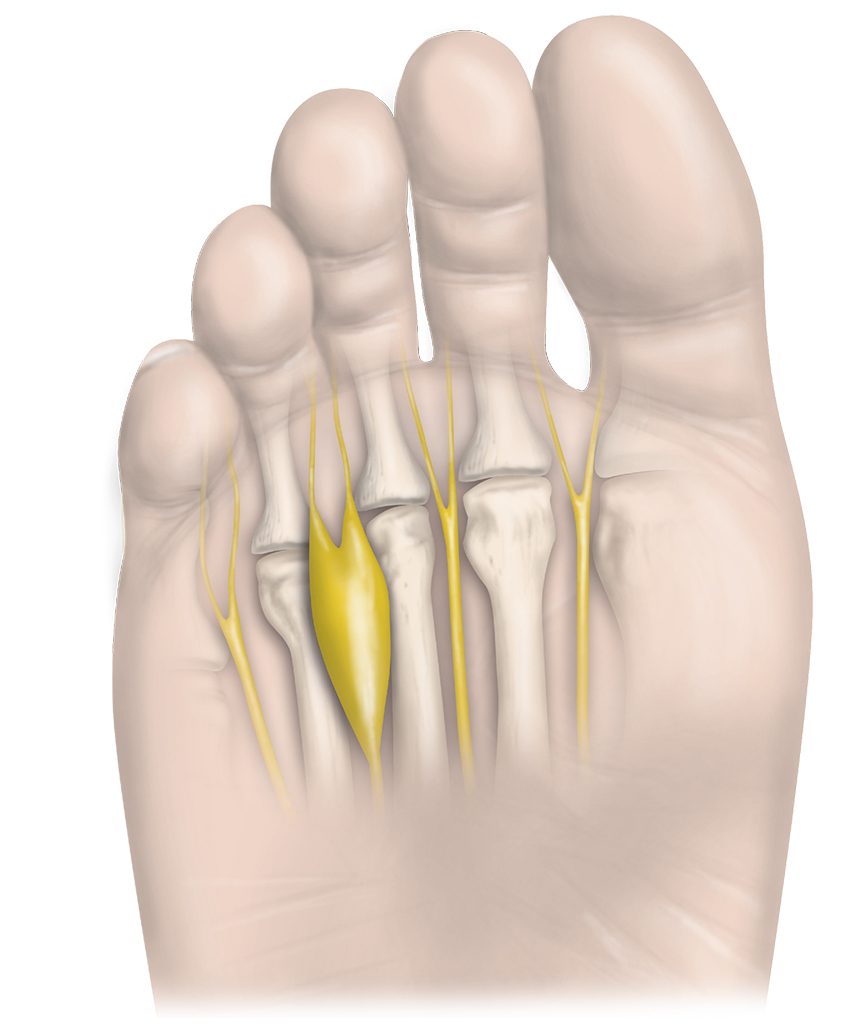

Patient med Mortons metatarsalgi i interdigitalnerv IV. Tillståndet kännetecknas av kompression och förtjockning/svullnad av fotens interdigitalnerver som bland annat kan orsaka neuropatisk, utstrålande smärta.

Mortons metatarsalgi är en degenerativ neuropati till följd av långvarig kompression och irritation av interdigitalnerven, som komprimeras mot de distala ändarna av metatarsalligamenten i samband med dorsalflexion av tårna [6, 7]. Den vanligaste lokalen innefattar oftast interdigitalnerven mellan tredje och fjärde metatarsalbenen då detta utrymme är trångt, men även nerverna mellan de övriga metatarsalbenen kan drabbas, vilket dock är mindre vanligt [7]. Fyra veder­tagna patogenetiska teorier är repetitiv stress av framfoten (som vid fotboll, löpning och balett), inflammation av intermetatarsalbursan, kompression av det djupa transversala intermetatarsalligamentetet och ischemi av vasa nervorum [5, 8, 9].